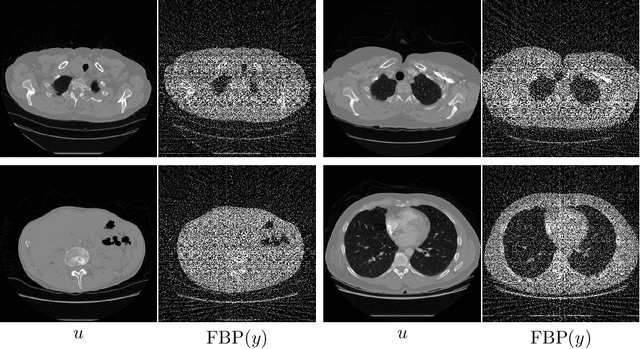

Abstract:In recent years the use of convolutional layers to encode an inductive bias (translational equivariance) in neural networks has proven to be a very fruitful idea. The successes of this approach have motivated a line of research into incorporating other symmetries into deep learning methods, in the form of group equivariant convolutional neural networks. Much of this work has been focused on roto-translational symmetry of $\mathbf R^d$, but other examples are the scaling symmetry of $\mathbf R^d$ and rotational symmetry of the sphere. In this work, we demonstrate that group equivariant convolutional operations can naturally be incorporated into learned reconstruction methods for inverse problems that are motivated by the variational regularisation approach. Indeed, if the regularisation functional is invariant under a group symmetry, the corresponding proximal operator will satisfy an equivariance property with respect to the same group symmetry. As a result of this observation, we design learned iterative methods in which the proximal operators are modelled as group equivariant convolutional neural networks. We use roto-translationally equivariant operations in the proposed methodology and apply it to the problems of low-dose computerised tomography reconstruction and subsampled magnetic resonance imaging reconstruction. The proposed methodology is demonstrated to improve the reconstruction quality of a learned reconstruction method with a little extra computational cost at training time but without any extra cost at test time.